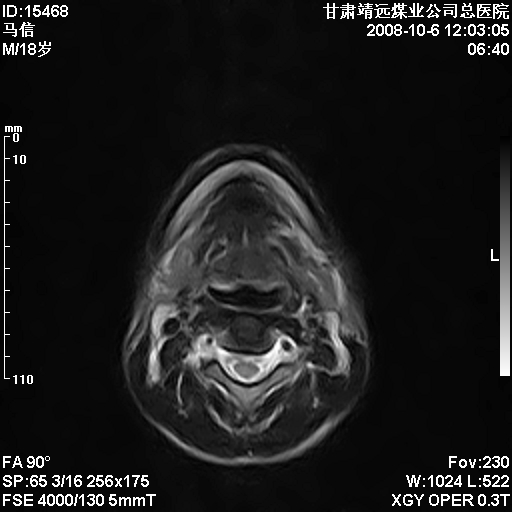

患者18岁,学生,在玩耍中受伤来检查,患者喜欢打篮球。颈椎内异常信号影,我们考虑占位,但是不像占位,又考虑硬膜囊的增厚,大家关建看颈椎椎管内的那个异常占位信号

脑脊液流动伪影?

是正常的脑脊液波动伪影

脑脊液流动伪影

你说的占位是伪影。在我们医院1.5t和3.0t的mr上是经常看见的。